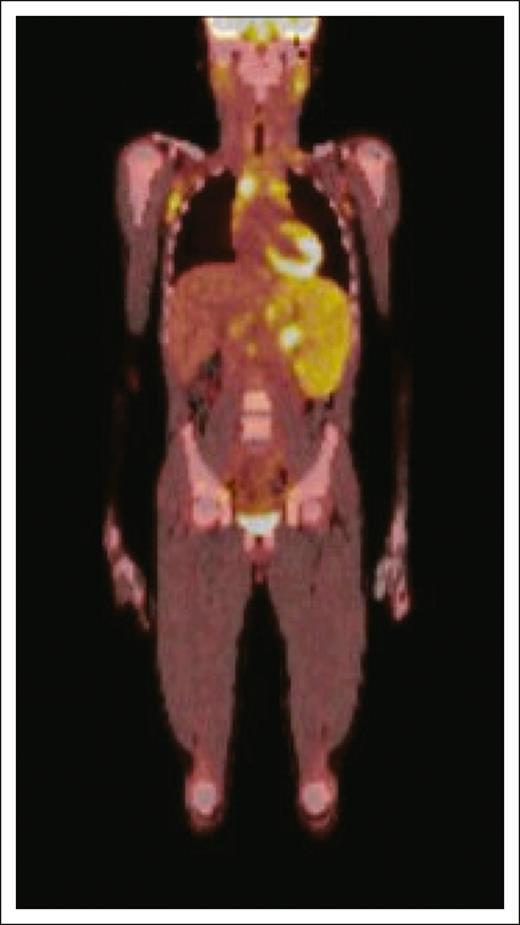

In children, the median age at presentation is ∼8 to 12 years.6,9-11 Disease often presents with advanced stage and diffuse involvement including peripheral lymph nodes, mediastinal and intra-abdominal nodes, liver, spleen, bone marrow, and other extranodal sites (Figure 3). In children, this can include any combination of nodal, extranodal, and/or systemic/leukemic disease.6,7,9-11,46 Many also present with B symptoms. Patients may develop malignant effusions, including pleural and pericardial effusions. Laboratory tests often reveal elevated lactate dehydrogenase (LDH).9 Paraneoplastic features including hemophagocytosis with systemic inflammation, pruritis, or eosinophilia can be seen from inflammation of T-cell cytokine production.6 Central nervous system (CNS) involvement, although rare, has been described.9,47-49

Radiographic depiction of clinical presentation of PTCL-NOS. Positron emission tomography scan reveals diffuse nodal and extranodal disease including involvement of axillary and inguinal nodes, parotid glands, anterior mediastinal mass, and spleen, as well as suggestion of bone marrow involvement in a pediatric patient with PTCL-NOS at initial presentation.